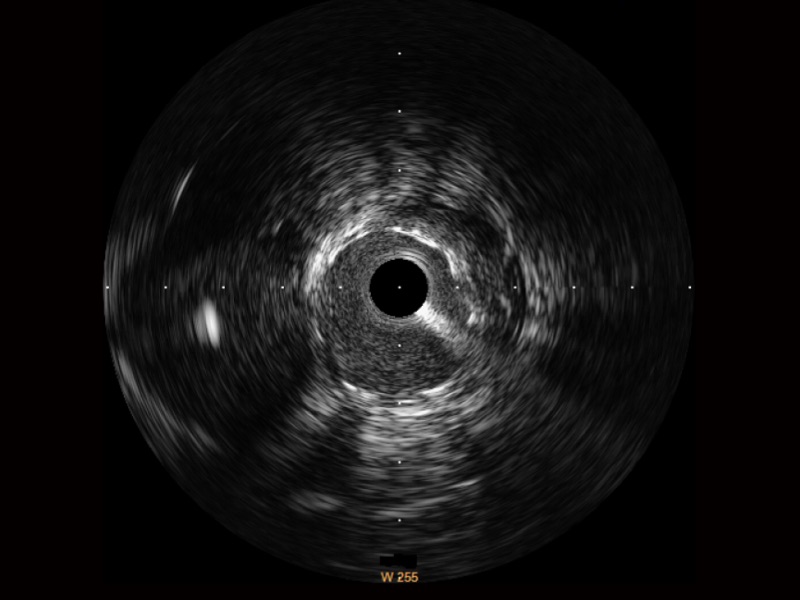

血管内超声(IVUS) 通过对病变程度、性质和累及范围的精确判断,可帮助选择治疗策略和方法,指导介入治疗过程,能够降低主要不良心血管事件,改善预后,在复杂病变介入治疗中用于指导支架置入的优势更为明显。血管内超声(IVUS)已成为精准心血管介入治疗的“金标准”。

对比传统IVUS导管成像,db真人体育官网宽频IVUS图像的近场支架梁显影更细腻,远场中膜外血管仍清晰可辨,兼顾远中近,兼顾分辨力与穿透深度